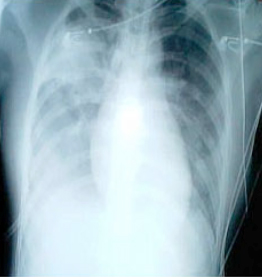

SARS患者患病八天的胸透照片